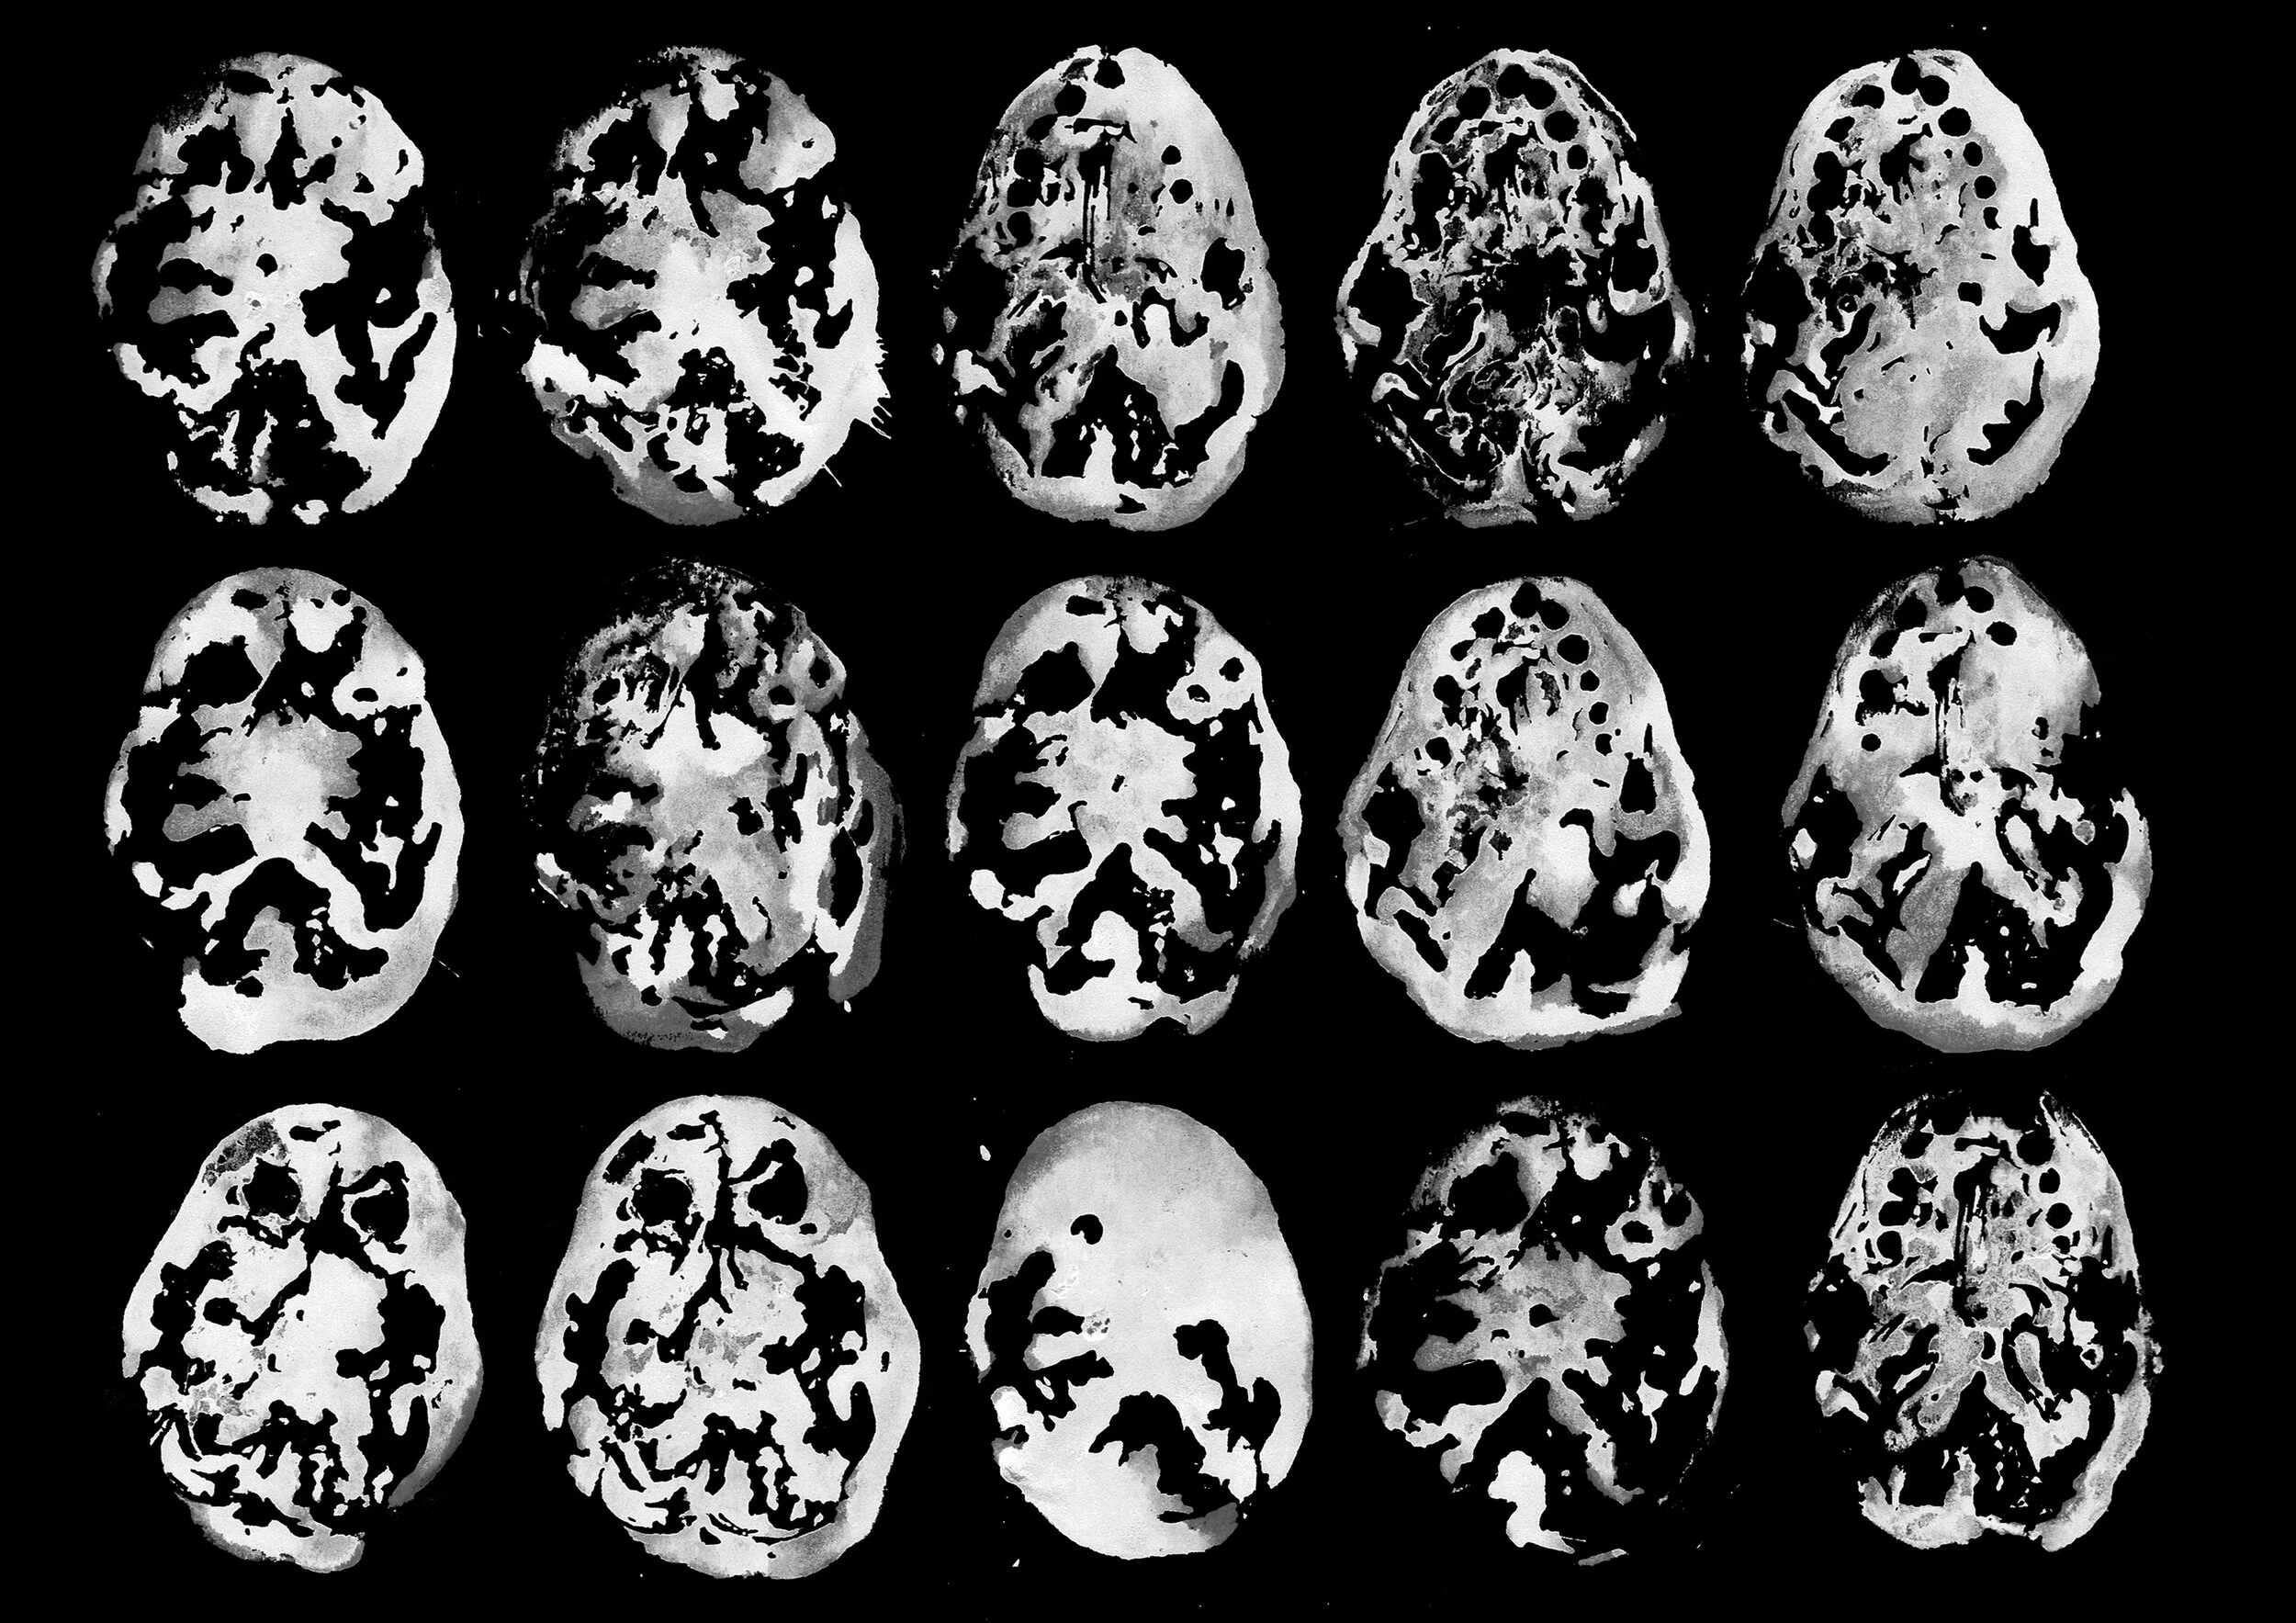

Prints made from personal MRI scans of tumour